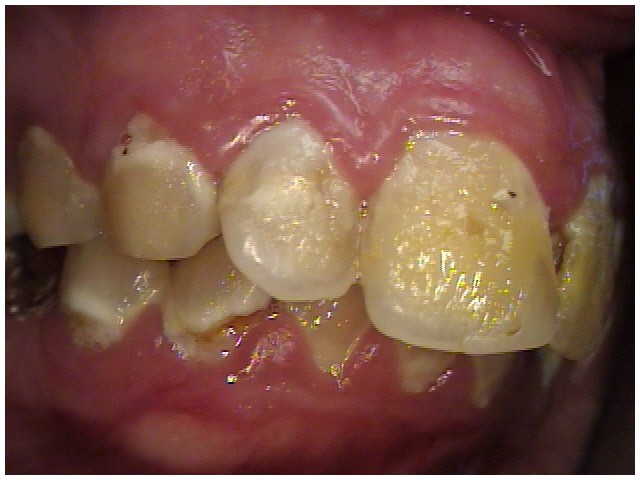

Often, the most visually striking manifestation of long-term meth use—known as “meth mouth”—is caused by the lack of saliva combined with an increase in soda drinking and extremely poor oral hygiene. This typically leads to meth abusers experiencing a large amount of caries. Decay begins with occlusal and facial caries and progresses rapidly, decaying to the bone level and often leaving only roots (Figure 1 through Figure 3).16

Fig 4 through Fig 6. Patient’s oral condition after 6 years of meth use.

Figure 4